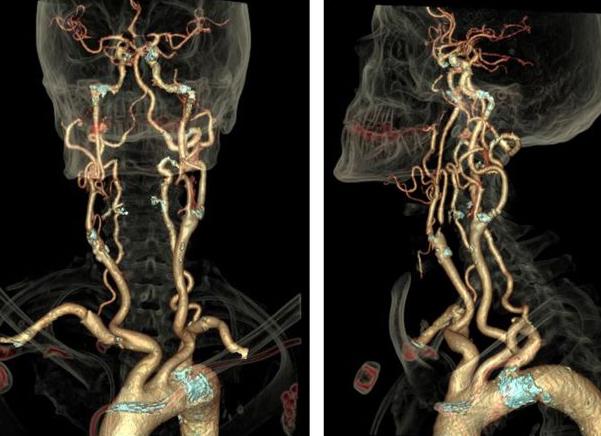

Визуализировать органы шеи и мягкие ткани очень сложно на рентгене, для этого применяются контрасты, да и то диагноз выставляют косвенно. Революционным открытием в этом направлении стало МРТ (магнитно-резонансная томография), она позволяет увидеть патологию мягких тканей. У человека в области шеи, головы есть много органов, сосудов, нервов, которые необходимо визуализировать, чтобы установить точный диагноз. Проведенное МРТ шейного отдела, головы позволяет это сделать наиболее качественно и оптимально.